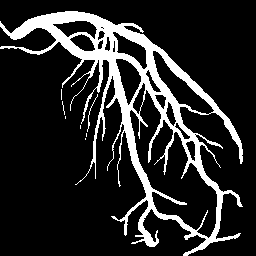

Blood vessel segmentation is crucial for many diagnostic and research applications. In recent years, CNN-based models have leaded to breakthroughs in the task of segmentation, however, such methods usually lose high-frequency information like object boundaries and subtle structures, which are vital to vessel segmentation. To tackle this issue, we propose Boundary Enhancement and Feature Denoising (BEFD) module to facilitate the network ability of extracting boundary information in semantic segmentation, which can be integrated into arbitrary encoder-decoder architecture in an end-to-end way. By introducing Sobel edge detector, the network is able to acquire additional edge prior, thus enhancing boundary in an unsupervised manner for medical image segmentation. In addition, we also utilize a denoising block to reduce the noise hidden in the low-level features. Experimental results on retinal vessel dataset and angiocarpy dataset demonstrate the superior performance of the new BEFD module.